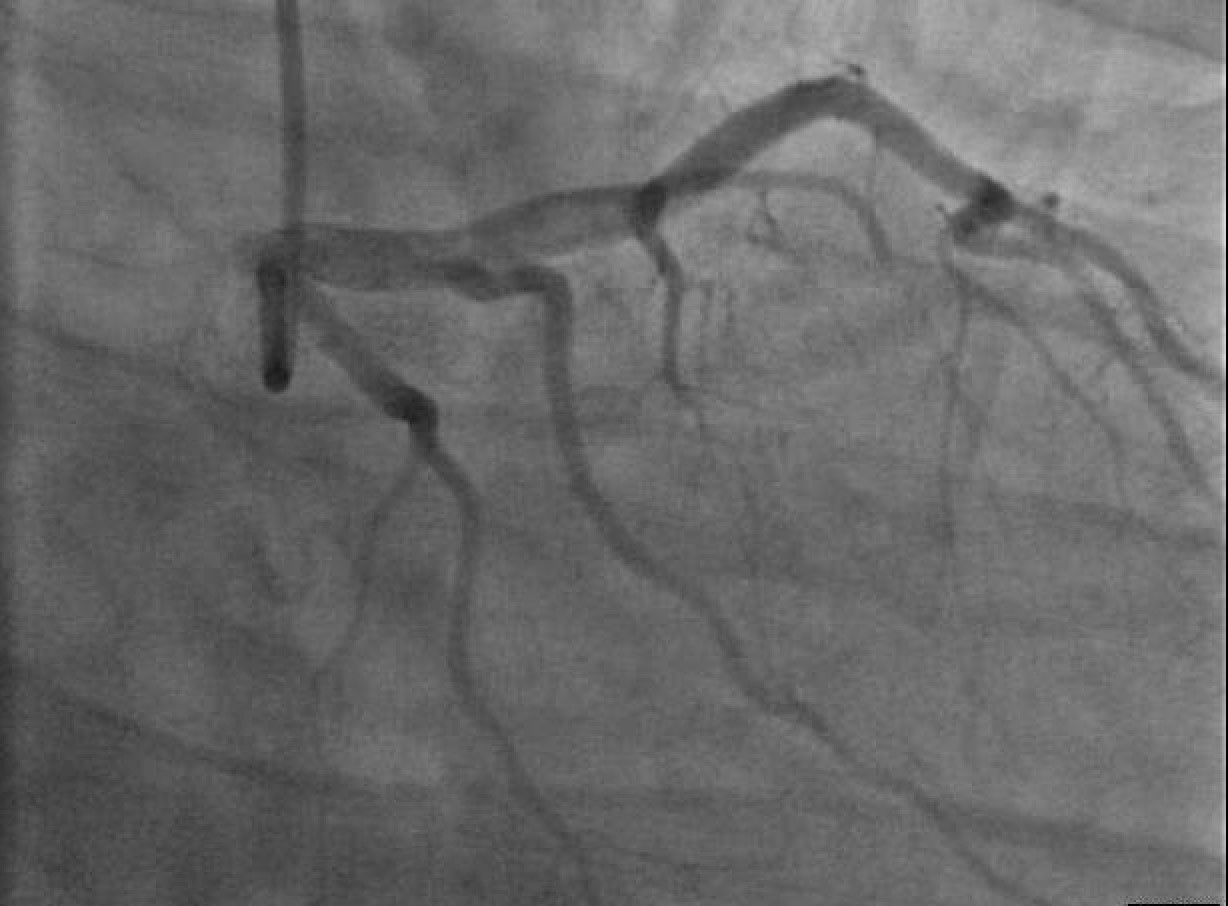

• Cardiac Catheterization: Proximal left anterior descending (LAD) artery thrombus with 70% stenosis and distal LAD occlusion. Patient was treated with unfractionated heparin and glycoprotein 2b/3a inhibitor (Tirofiban). [Figure 4]

• Second Catheterization: On the following day, residual LAD thrombus was identified with the help of Fractional Flow Reserve procedure. It was treated with a combination of intracoronary thrombolytic (Alteplase) and an aspiration thrombectomy. [Figure 5]